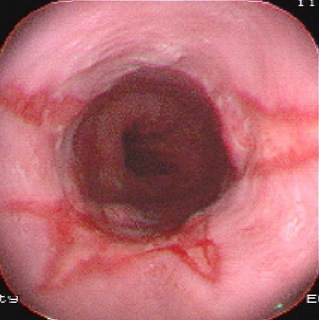

食管下段的鱗狀上皮被柱狀上皮覆蓋,因?yàn)橛薆arrett首先報(bào)道,因此稱 Barrett食管 ,中文翻譯為巴雷特食管。目前認(rèn)為是獲得性,可能與 反流性食管炎 相關(guān),并有發(fā)生 腺癌 的可能。其癥狀...

•   Barrett食管癥狀及檢查 日期:2016-05-02 17:16:00 點(diǎn)擊:2228 好評:37

常見癥狀 便血 惡心與嘔吐 燒心 吞咽困難 胸骨后疼痛 BE本身并無癥狀,其癥狀主要是由于胃食管反流及其并發(fā)癥所引起的,多數(shù)患者最初有GERD癥狀,如胃灼熱,反流,吞咽困難,常見癥狀多見...